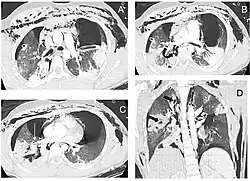

Reconstruction of the trachea and bronchi with x-ray computed tomography showing disruption of the right main bronchus with abnormal lucency (arrow)[1] | |

Chest x-ray is the initial imaging technique used to diagnose TBI.[17] The film may not have any signs in an otherwise asymptomatic patient.[15] Indications of TBI seen on radiographs include deformity in the trachea or a defect in the tracheal wall.[17] Radiography may also show cervical emphysema, air in the tissues of the neck.[2] X-rays may also show accompanying injuries and signs such as fractures and subcutaneous emphysema.[2] If subcutaneous emphysema occurs and the hyoid bone appears in an X-ray to be sitting unusually high in the throat, it may be an indication that the trachea has been severed.[4] TBI is also suspected if an endotracheal tube appears in an X-ray to be out of place, or if its cuff appears to be more full than normal or to protrude through a tear in the airway.[17] If a bronchus is torn all the way around, the lung may collapse outward toward the chest wall (rather than inward, as it usually does in pneumothorax) because it loses the attachment to the bronchus which normally holds it toward the center.[6] In a person lying face-up, the lung collapses toward the diaphragm and the back.[23] This sign, described in 1969, is called fallen lung sign and is pathognomonic of TBI (that is, it is diagnostic for TBI because it does not occur in other conditions); however it occurs only rarely.[6] In as many as one in five cases, people with blunt trauma and TBI have no signs of the injury on chest X-ray.[23] CT scanning detects over 90% of TBI resulting from blunt trauma,[3] but neither X-ray nor CT are a replacement for bronchoscopy.[6]